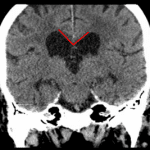

- Global ventriculomegaly and cerebral volume loss with a borderline steep callosal angle (~90 degrees, normal = 100-120 degrees) and confluent periventricular hypoattenuation

- Ex vacuo ventriculomegaly vs normal pressure hydrocephalus

Global ventriculomegaly which may represent ex vacuo dilation in the setting of diffuse cerebral volume loss. However, given confluent periventricular white matter hypoattenuation, a borderline steep callosal angle (~90 degrees, normal = 100-120 degrees), and the reported clinical history of frequent falls, normal pressure hydrocephalus should be considered.